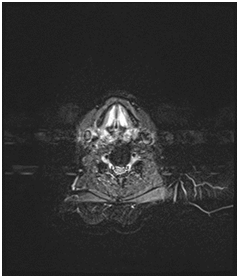

A 70 years old male patient presented to the emergency department with stridor and dysphagia of 3months duration. Patient was examined by fiber optic nasopharyngoscope which revealed supra-glottic mass to the left side with restricted mobility of the left vocal cord. Patient was admitted and submitted for urgent tracheostomy. MRI neck with contrast was done and revealed a Supraglottic mass measuring about 2cm X 1.5cm, partially occluding the airway and showing enhancement post gadolinium injection. It is appearing isointense in T1 and T2-weighted images with mildly enlarged vocal cords (Figure 1–3).  Panendoscopy was performed on 18/02/2018 and revealed a mass occupying the post cricoid area, pyriform fossa, supraglottic and the lateral pharyngeal wall. Base of the tongue, tonsils, right side of the larynx and the posterior pharyngeal wall were free.

Figure 2 MRI neck, axial cut, showing supraglottic mass lesion partially occluding the airway.

Figure 7 MRI neck, coronal cut, showing the old postoperative changes with right hemi glossectomy.